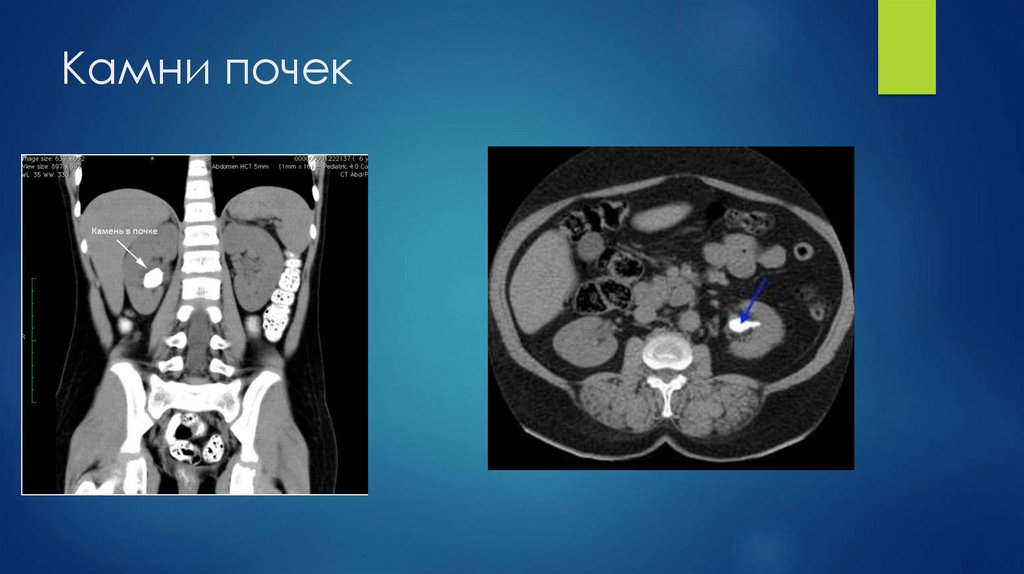

67. Камни почек